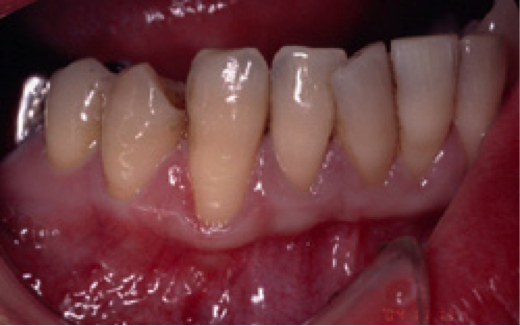

歯肉が全体的に下がっていることを主訴に来院されました。特にひどいのが右下の犬歯付近で、ここについては手術を受けてでも治したいとのことでした。このような状態を歯肉退縮と呼びますが、原因は大きく分けて二つ考えられます。一つは強く歯を磨きすぎること、もう一つは歯ぎしりなどの噛み合わせの不具合です。必ず事前の診査により原因を除去しておかないと、手術をして元通りになったとしても、またすぐに下がってしまいます。この症例では口蓋より結合組織を採取し、右下犬歯の部分に移植しました。

下は術後の状態です。術中の写真は痛々しいので割愛させていただきました。